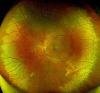

Fundus picture of the left eye showing concentric retinal whitening suggestive of commotio retinae.